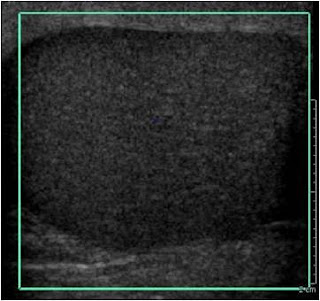

2-Findings:

-Enlarged testicle with diffuse hypo echoic pattern or it may be of multifocal hypo echoic areas.

-Many have normal testicular findings.

-Enlarged and hypo echoic epididymis.

-Scrotal skin thickening.

-Diagnosis was made by Doppler study of the blood flow reaching testicle.

-Scanning should be for at least one minute of duration without detection of blood flow reaching the testicle, or if there is a small single vessel in the symptomatic testicle when contralateral normal testicle shows diffuse flow.